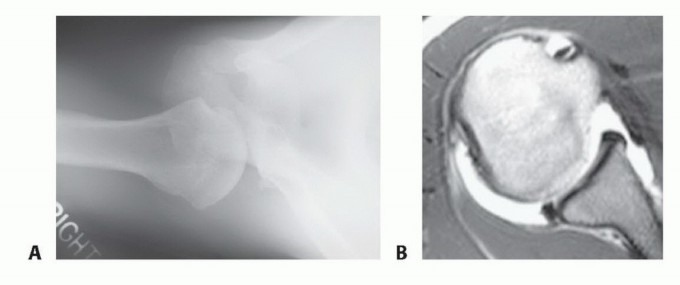

Arthroscopic Treatment of Posterior Shoulder Instability DEFINITION Posterior shoulder instability results in…